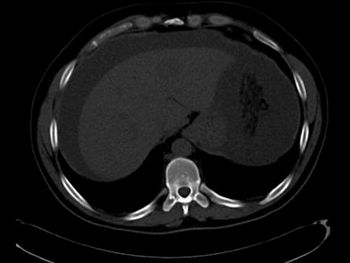

A 37-year-old Lebanese male with no significant past medical history initially presented with an increase in abdominal girth over a few weeks with worsening shortness of breath, nausea, and intermittent vomiting.